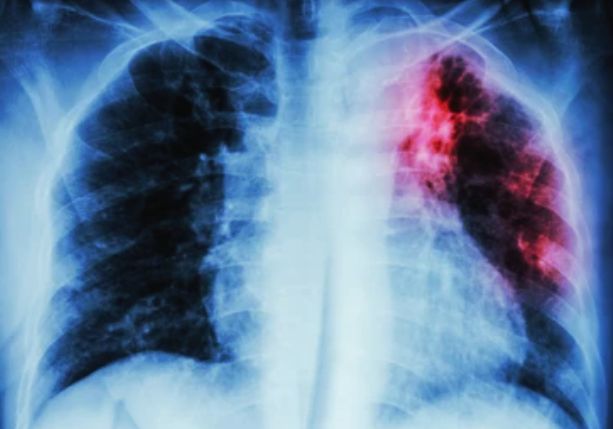

The ultraportable digital chest X-ray, developed by South Korean firm Poskom, weighs a mere 5 kg (approximately 11 lbs) and is equipped with AI-driven computer-aided detection software.

To enable diagnosis of TB, this technology interprets X-rays with an accuracy comparable to expert radiologists, paving the way for early screening and triage outside traditional health facilities. This breakthrough addresses long-standing challenges of distance, cost, and stigma that many face when seeking care.